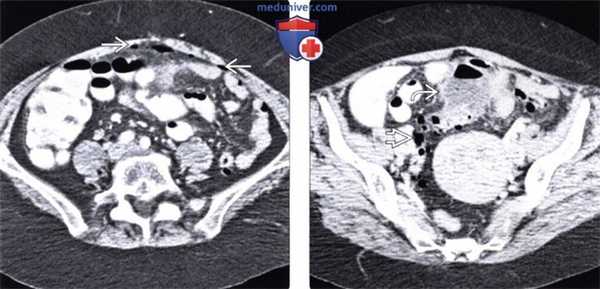

(Слева) На аксиальной КТ с контрастным усилением у пациентки с симптомами в виде умеренно выраженных болей в животе, лихорадки, болезненности определяется большое количество свободного газа внутри полости брюшины.

(Справа) На аксиальной КТ с контрастом у этой же пациентки выявлен многокамерный абсцесс, тесно прилежащий к сигмовидной кишке, измененной за счет выраженного дивертикулеза, что и послужило причиной свободного газа и абсцесса.

(Слева) На аксиальной КТ с контрастным усилением у пожилой женщины после РХПГ и пап ил-лотомии визуализируется большое скопление газа и жидкости в забрюшинном пространстве, особенно в переднем околопочечном пространстве и в области межфасциальной пластинки.

(Справа) При аксиальной КТ с контрастом у этой же пациентки выявлен забрюшинный абсцесс. Перфорация произошла во втором отделе двенадцатиперстной кишки в зоне оперативного вмешательства (папиллотомии). (Слева) При аксиальной КТ с контрастным усилением у молодой женщины с прогрессирующей лихорадкой и болью в животе в течение многих дней определяется большой периаппендикулярный абсцесс, оказывающий объемное воздействие на тонкую кишку, мочевой пузырь и матку, смещающий их в сторону.

(Справа) На аксиальной КТ с контрастом у пациента после холецистэктомии в ложе удаленного желчного пузыря визуализируется скопление газа с крайне малым количеством жидкости. Также видны клипсы. Это не абсцесс; так выглядит препарат оксидированной целлюлозы (сержисел), помещенный в ложе желчного пузыря во время операции с целью остановки кровотечения.